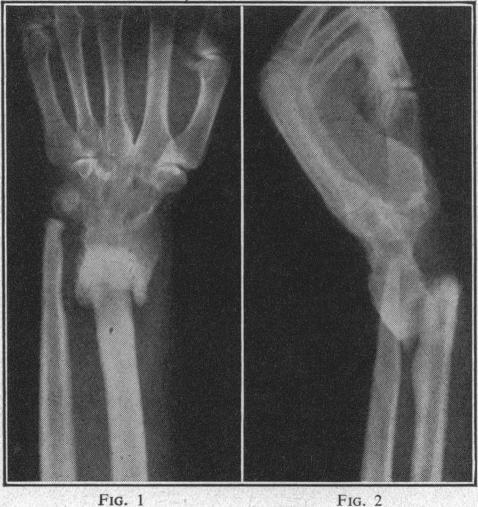

The artificial wrist: intentional pseudoarthrosis in Colles's fracture.

Colles's fracture.

Colles' fractures.